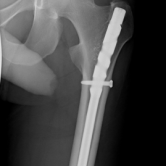

Röntgenbilder